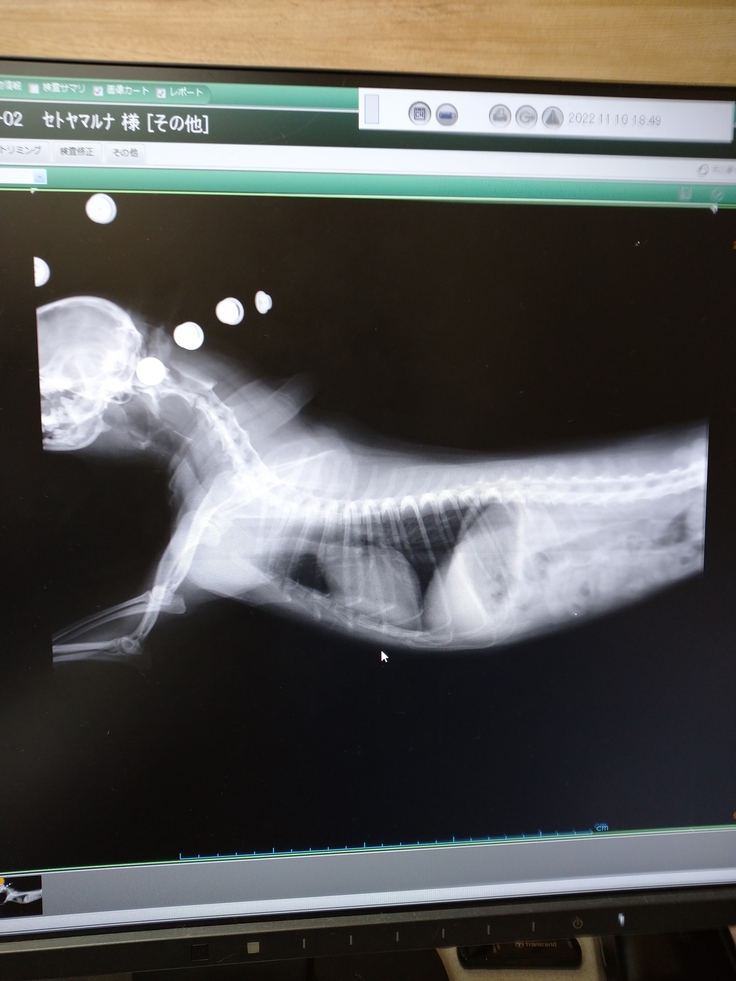

▲レントゲンは11月に動物病院に許可をもらい、撮らせて頂いたものです。

※名称は動物病院の希望により伏せてますが、資料の掲載許可は得ています。

内視鏡検査を2022年11月にした結果、かなり進行しており、重度のグレード4に相当し、90%以上の虚脱が見られ、ほぼ閉塞していました。

また胸部付近まで虚脱が見られ、気管が潰れて窒息死してしまう可能性が高いという診断でした。